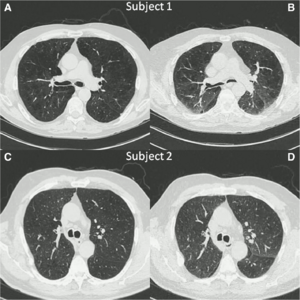

Airway Wall Thickness is Increased in COPD Patients with Bronchodilator Responsiveness

Publication: Respir Res. 2014 Aug 8;15:84. PMID: 25248436 | PDF Authors: Kim V, Desai P, Newell JD, Make BJ, Washko GR, Silverman EK, Crapo JD, Bhatt SP, Criner GJ; COPDGene Investigators. Institution: Temple University School of Medicine, Philadelphia, PA, USA. Background/Purpose: Bronchodilator responsiveness (BDR) is a common but variable phenomenon in COPD. The CT characteristics of airway dimensions that differentiate COPD subjects with BDR from those without BDR have not been well described. We aimed to assess airway dimensions in COPD subjects with and without BDR. Methods: We analyzed subjects with GOLD 1-4 disease in the COPDGene® study who had CT airway analysis. We divided patients into two groups: BDR + (post bronchodilator ΔFEV1 ≥ 10%) and BDR-(post bronchodilator ΔFEV1 < 10%). The mean wall area percent (WA%) of six segmental bronchi in each subject was quantified using VIDA. Using 3D Slicer, airway wall thickness was also expressed as the square root wall area of an airway of 10 mm (Pi10) and 15 mm (Pi15) diameter. %Emphysema and %gas trapping were also calculated. Results: 2355 subjects in the BDR-group and 1306 in the BDR + group formed our analysis. The BDR + group had a greater Pi10, Pi15, and mean segmental WA% compared to the BDR-group. In multivariate logistic regression using gender, race, current smoking, history of asthma, %emphysema, %gas trapping, %predicted FEV1, and %predicted FVC, airway wall measures remained independent predictors of BDR. Using a threshold change in FEV1 ≥ 15% and FEV1 ≥ 12% and 200 mL to divide patients into groups, the results were similar. Conclusion: BDR in COPD is independently associated with CT evidence of airway pathology. This study provides us with greater evidence of changes in lung structure that correlate with physiologic manifestations of airflow obstruction in COPD. Funding:

- 1.20 Airway Wall Thickness is Increased in COPD Patients with Bronchodilator Responsiveness

- 1.36 Clinical and Computed Tomographic Predictors of Chronic Bronchitis in COPD: A Cross Sectional Analysis of the COPDGene Study